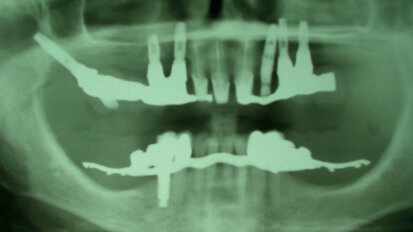

Caso clinico di odontoiatria forense relativo a un piano riabilitativo complesso implantare

Riportiamo alcune considerazioni su un case report descritto da un odontologo forense con oltre trent’anni di esperienza, tacendo, per ovvi motivi di ...